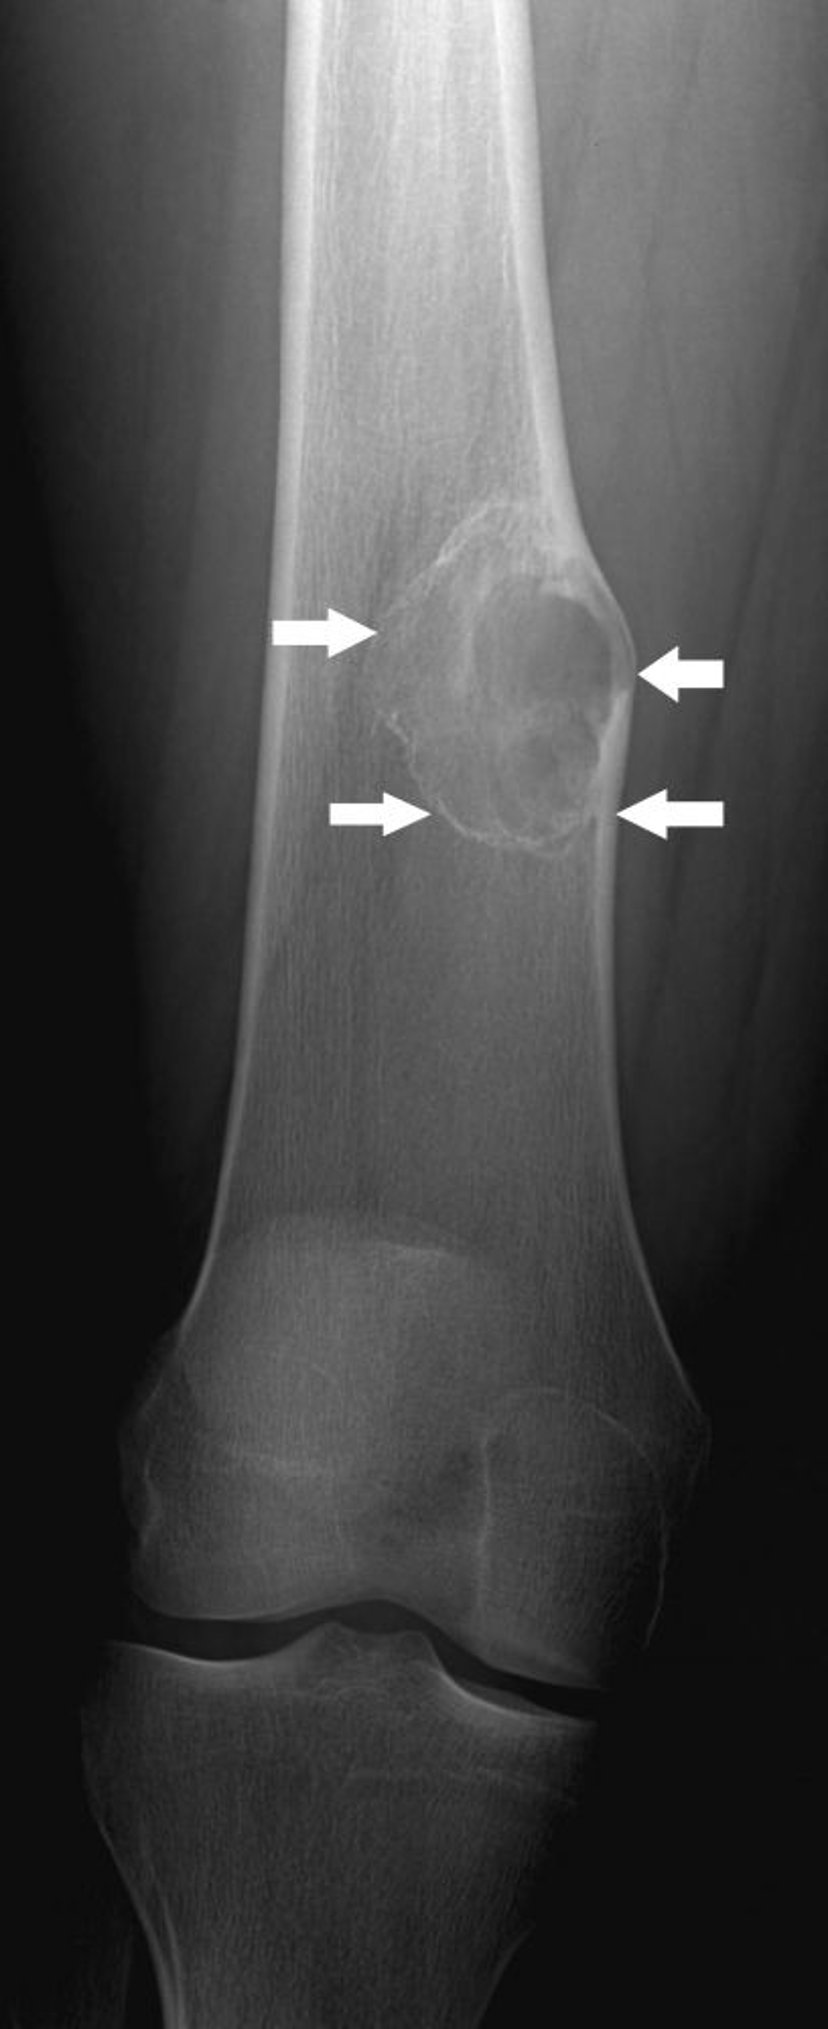

Fibroma não ossificante

Esta radiografia mostra um fibroma não ossificante (setas) acima do joelho no osso da coxa.

Imagem por cortesia do Dr. Michael J. Joyce e do Dr. Hakan Ilaslan.